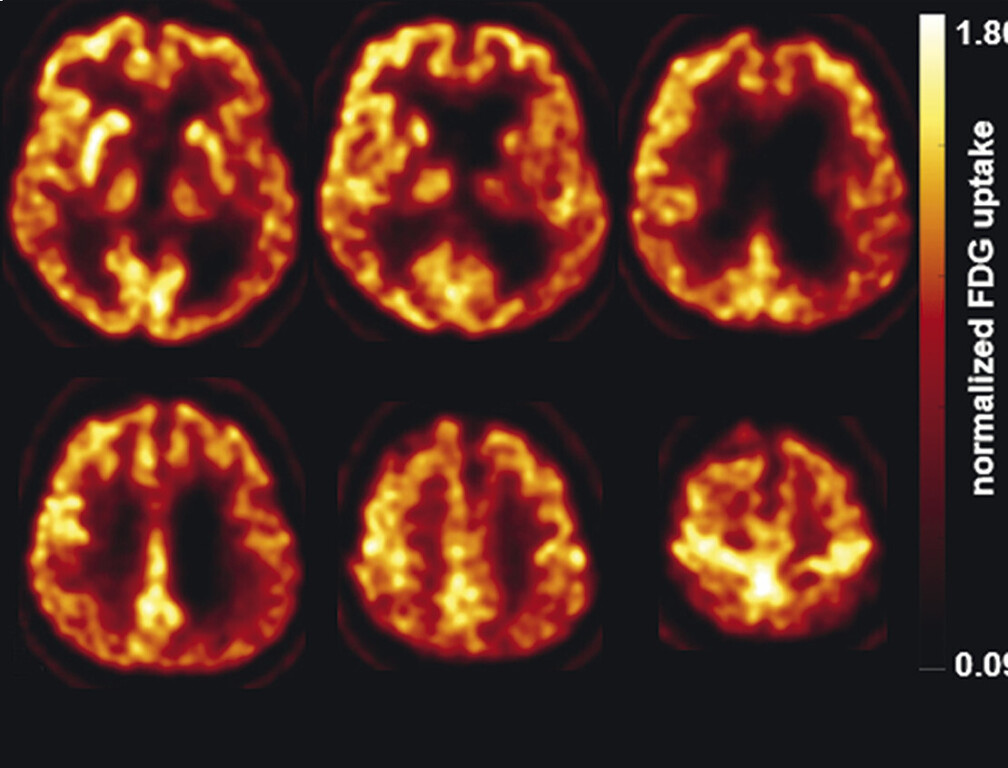

- Einen diagnostischen Mehrwert in der Parkinson-Frühdiagnostik hat die FP-CIT-SPECT. Dabei wird mithilfe eines radioaktiven Markers die präsynaptische Dopamintransporterbindung dargestellt, die bei der Parkinson-Erkrankung reduziert ist. Es ist jedoch zu beachten, dass mit der FP-CIT-SPECT keine Abgrenzung von einem atypischen Parkinson-Syndrom möglich ist. Zur Differenzialdiagnose eines atypischen Parkinson-Syndroms kann die FDG-PET bzw. die Tau-PET eingesetzt werden. Mit der FDG-PET werden regionale Veränderungen des zerebralen Glukosestoffwechsels und damit krankheitsspezifische neurodegenerative Prozesse dargestellt. Die Tau-PET hilft bei der Differenzialdiagnose von Tauopathien wie z.B. der progressiven supranukleären Blickparese oder der kortikobasalen Demenz.

62-jähriger Mann mit über 3 Jahre zunehmender Bewegungsverlangsamung und unsicherem Gangbild. Die MP-RAGE-Aufnahmen zeigen eine deutliche Mittelhirnatrophie mit Kolibri- (a) und Mickey-Mouse-Zeichen (b). Das Mittelhirn/Pons-Verhältnis liegt mit 0,15 im pathologischen Bereich (Normalwert ca. 0,24). Die voxel- und regionenbasierte morphometrische Analyse (c) zeigt neben der Mittelhirnatrophie eine links-frontomesial betonte Atrophie, das FDG-PET (e) einen Hypometabolismus dieser Regionen. Dieses Muster ist typisch für eine sog. Tauopathie und unterstützt daher die Diagnose progressive supranukleäre Parese mit Richardson-Syndrom.

e FDG-PET. (mit freundlicher Genehmigung von Prof. Dr. Dr. P.T. Meyer, Klinik für Nuklearmedizin Uniklinik Freiburg)

61-jähriger Mann mit rechtsbetonter Gliedmaßenapraxie, sodass Schreiben und Zeichnen nicht mehr möglich sind. MP-RAGE-Aufnahmen (a–c) zeigen eine deutliche Atrophie der linken Großhirnhemisphäre mit Ausziehung vor allem der Cella media des linken Seitenventrikels. Die voxel- und regionenbasierte morphometrische Analyse (d) bestätigt die Atrophie mit Betonung des Parietallappens. Die FDG-PET (e) zeigt einen Hypometabolismus der linken Hemisphäre mit Beteiligung von Thalamus und Basalganglien. Klinische Symptomatik und Bildgebung sind passend für eine kortikobasale Degeneration.